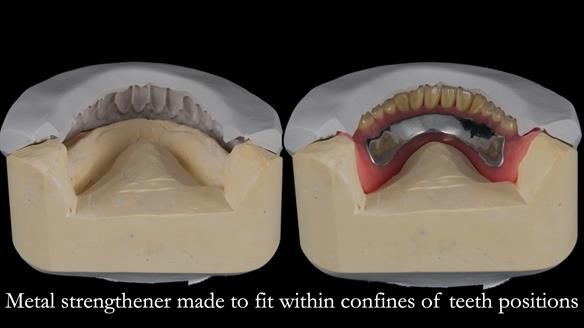

The detailed clinical situation and treatment process are outlined below, with clinical work provided by me and technical work by Rowan Garstang. The treatment spanned 12 months, involving removing 5 upper anterior teeth, adding to an existing upper RPD, followed by creating and fitting metal based complete dentures.